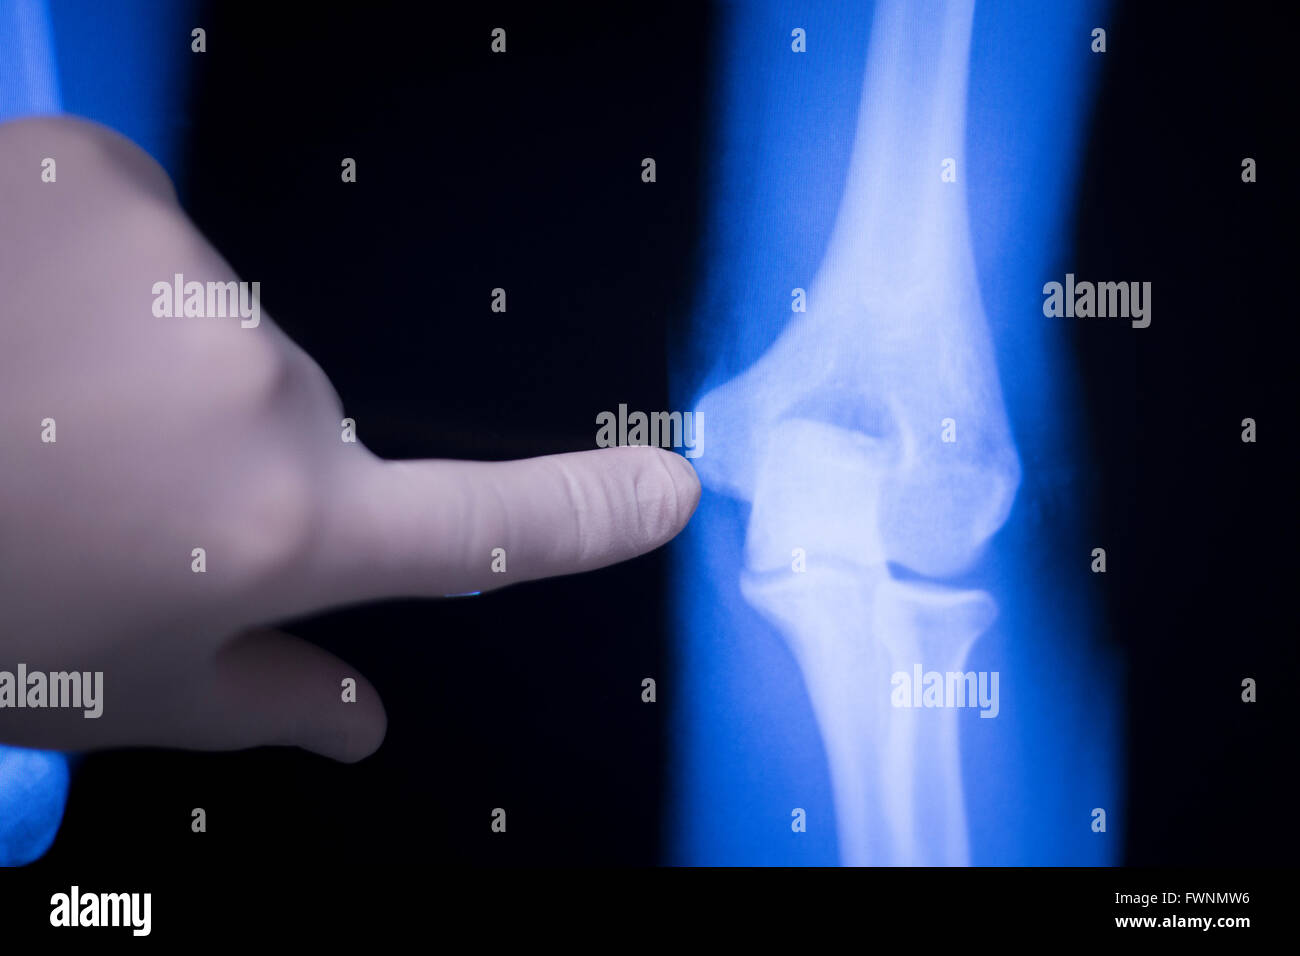

From www.alamy.com

Elbow, forearm and arm joint medical xray test scan result for senior Arthritis In Elbow And Forearm If you are experiencing pain, swelling and stiffness in the elbows, you may have one of the following types of arthritis or related conditions. Ulna, the forearm bone on the pinky finger side. One sign that your elbow pain is ra is that you have symmetrical pain in both elbows. Osteoarthritis of the elbow occurs when the cartilage surface of. Arthritis In Elbow And Forearm.